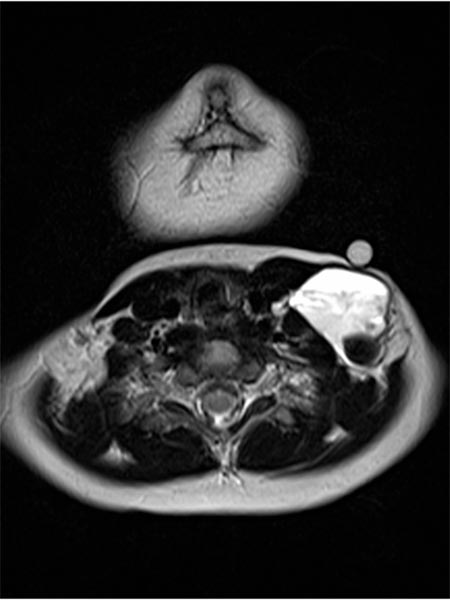

Axial MRI (T2-weighted) also shows the dorsal location of the larger hypointense thrombus within the severely hyperintense venous malformation. In addition, a classic fluid-fluid level within the venous malformation is depicted. The heavier corpuscular components with somewhat lower signal intensity settle dorsally with gravity (dorsal position), the liquid blood serum with somewhat higher signal intensity "floats" up (ventral position), and a fluid-fluid level forms in between.

Axial MRI (T1-weighted) at the same level after contrast administration shows central enhancement within the venous malformation. However, this enhancement is relatively slow (“pooling”) and detectable only minutes after contrast injection and is still incomplete at the time of imaging.